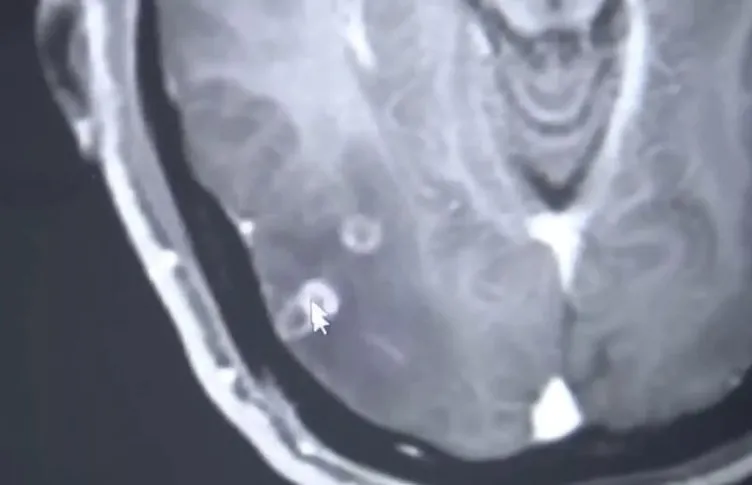

Çin'de bir adam, domuz eti yedikten sonra yoğun baş ağrısı yaşasa ve nöbet geçirse de doktora görünmeyi erteleyerek bir ay boyunca bu şekilde hayatına devam etti. Sonunda doktora gittiğinde ise beyni de dahil olmak üzere vücudunun her yerinde 700'den fazla tenya bulunduğu keşfedildi.

Bulaşıcı hastalıklar bölümünden Dr Wang Jian-rong, Bay Zhu'nun tıbbi muayenesini yaptı ve ona tenyazis teşhisi koydu. Ayrıca hastanın vücudunda 700'den fazla tenya bulundu.

Dr. Wang, şunları söyledi: "Hastanın beyninde çok sayıda yer kaplayan lezyon var. Bu lezyonlar aynı zamanda akciğerlerde de var ve göğüs boşluğunun içindeki kasları dolduruyor."

Enfeksiyonların halihazırda hastanın organlarına 'hasar verdiğini' de sözlerine ekledi.